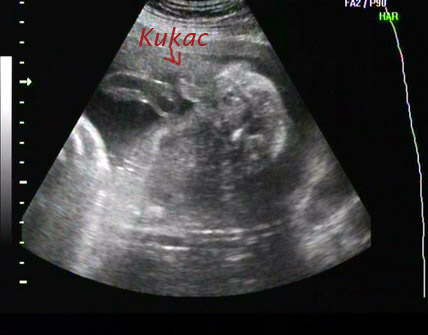

Hahó hahó!!Most értem csak ide!De hulla vagyok ugyh a többit holnap!Meg holnap még csinálok jobb képeket a dvd-ről!Most a lényeg!!Hogy ha minden igaz heréink vannak és kukink! :D :D :wink: FIU!!!!Itt az 1ik bizonyíték..ha látható!Meg egy arcos,ez nem a legjobb de gyors ezt sikerült!Holnap majd leírok mindent és teszek fel sok képet! :)

Szeríntetek is ez kuki?Vagy csak a doki látta így??De a heréket már csak nem téveszti el ott mellette.. :D :D

Missi: Gratulálok a kisfiúhoz! Ezt a dokik nem szokták eltéveszteni..ha ott van a kukaca, akkor nincs mese.. :lol:

Missi! Gratula a kukishoz, én lányra szavaztam :roll: Tényleg, van már neve????

Hali!!Most már tuti fiu,mert ma a dokim is megnézte(mivel multkor megígérte..és Ő nem tudja h voltam 4D-n :wink: )..és kérdezte h hát mit szeretnék??Mondom inkább fius vagyok!!Erre Ő:"Hát akkor igaza lesz!!Mert ott volt a kuksi!! :D :D